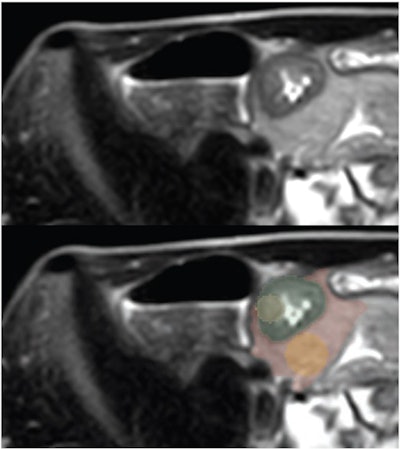

The study included data from 135 patients suspected of ileal Crohn's disease who underwent MR enterography (MRE) between December 2018 and October 2021; of these, 70 were eventually diagnosed with the condition. One radiologist chose two slices from each axial T2-weighted single-shot fast-spin echo (SSFSE) image that showed the greatest ileal wall thickening, then segmented four regions of interest and extracted radiomic features from these.

Three pediatric abdominal radiologists flagged the presence of ileal Crohn's disease on these SSFSE images. The study's reference standard was the clinical diagnosis of ileal Crohn's disease following positive endoscopy and biopsy, the group explained.